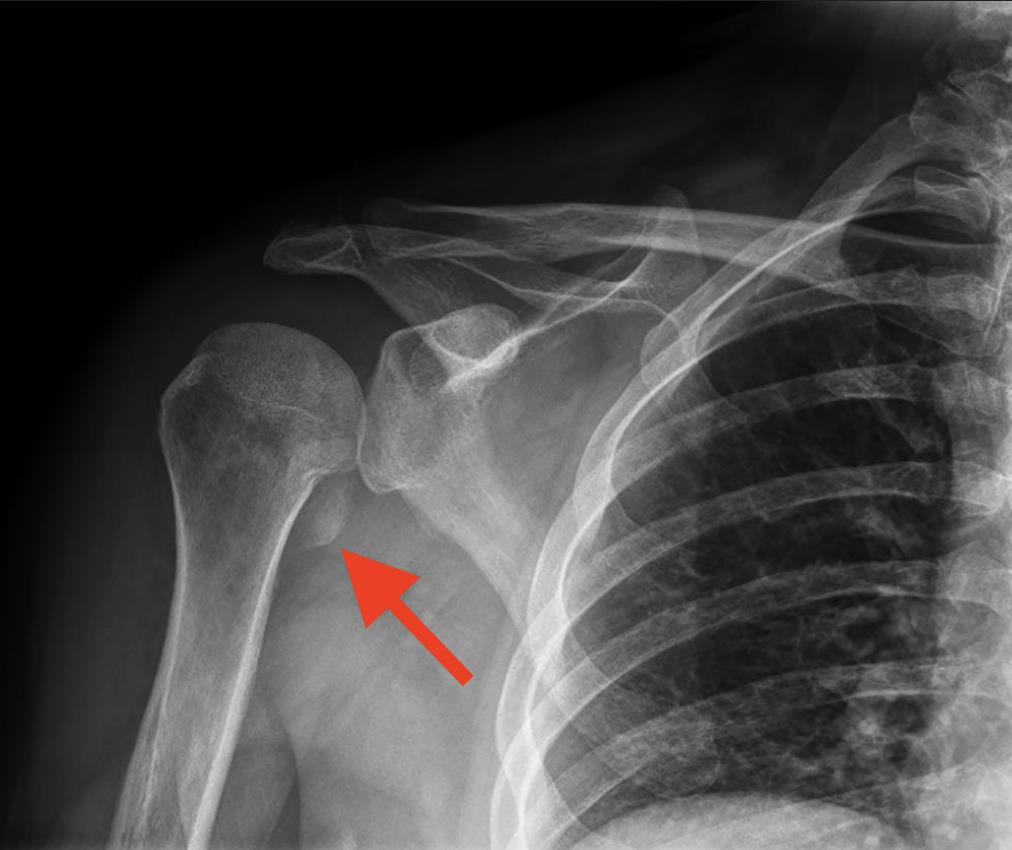

A 23-year-old firefighter falls from a ladder after being electrocuted by a live wire while doing practice drills on a firetruck. Radiographs of the right shoulder are shown in Figure A. Which of the following is particularly important to ascertain from the history or physical exam in the setting of this specific injury?